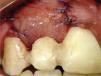

Regeneración ósea guiada con membrana de colágena reabsorbible 15×20mm (BIOMEND®), y xenoinjerto óseo 1g 500-1,000μ (BIOCRISS®).

La finalidad de estos pasos fue preservar la arquitectura ósea para la posterior colocación del implante (Figura 5).

Cirugía plástica mucogingival con instrumentos rotatorios, bola de diamante de baja velocidad (801.314035) (Edenta®, Suiza) (Figura 9). Teniendo como objetivo desvanecer en la encía queratinizada las cicatrices de las cirugías previas.